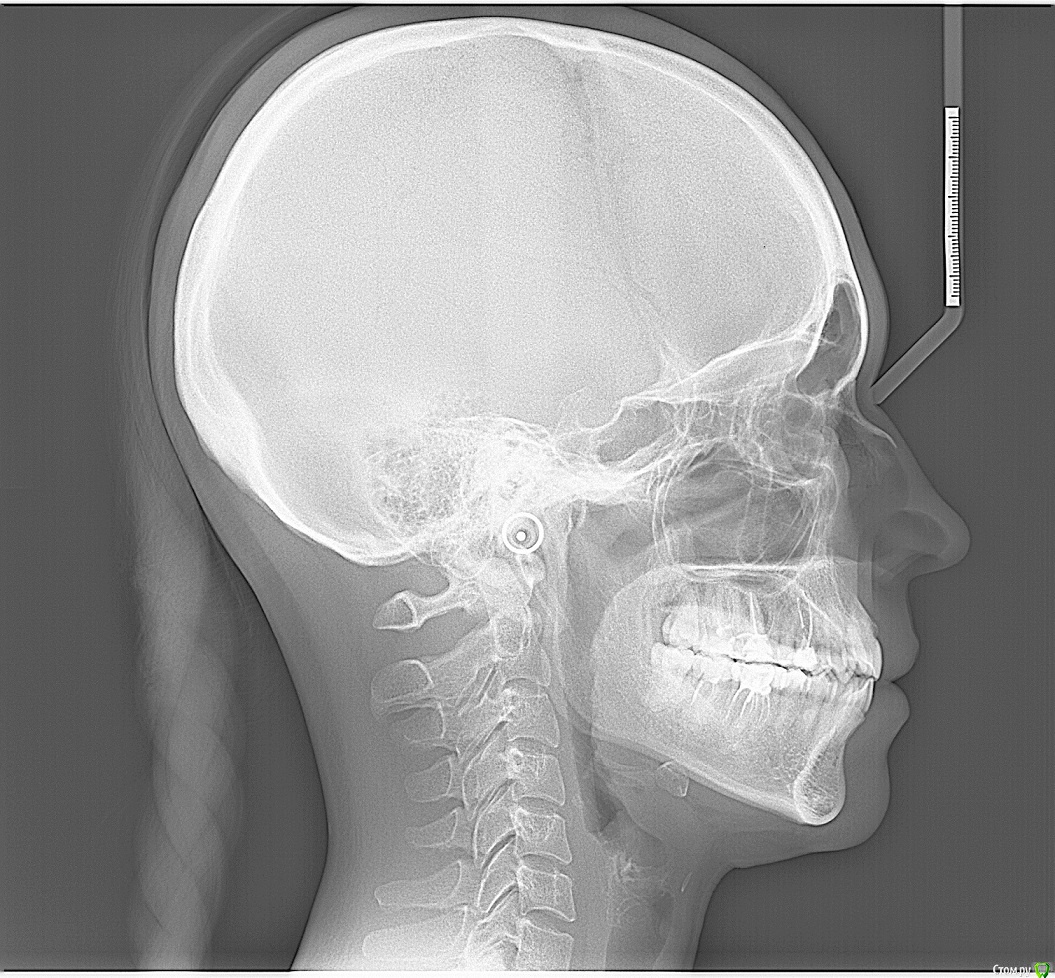

После лечения жевательных зубов на нижней и верхней челюсти начался дискомфорт в прикусе. Врач подшлифовал пломбы, начались боли в мышцах. Попробывал завысить, стало еще хуже. Через месяц начались щелчки с левой стороны, боли усиливались в районе жевательных мышц. Пробывали капы, результатов не давало. Сейчас не могу ни переживать толком еду, спать вообще не удобно. челюсть в обычном положении зафиксировать не могу, жевательных мышц совсем не чувсвую,разговаривать тоже не удобно, слюну ковтать трудно.Сильно напряжены мышцы возле носа, сзади головы и шеи, раслабить никак не могу. Начались сильные головные боли, боли в шее, в левой лопатке.  Сделали мрт шейного отдела, показало деформация шейного отдела и грыжи. Стоматологи говорят что это из-за прикуса. К кому обратиться помогите,Есть фотография до лечения, прикрепляю.

КТ даёт лишь информацию относительно костных структур сустава, а хотелось бы увидеть что там со связками, но для этого нужно МРТ. Со стороны костных структур я не увидел каких-то критических изменений, за исключением может быть ремоделирования суставных поверхностей.